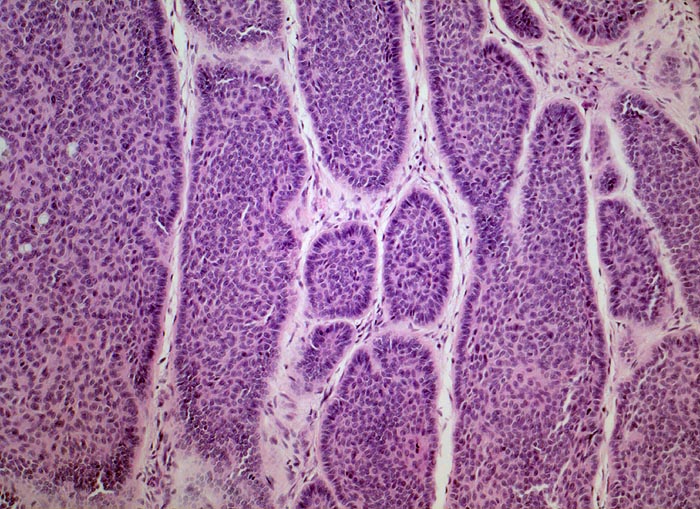

Basaliom

maligner Tumor

Haut, Kopf

Der Tumor besteht aus soliden Platten aus basaloiden Zellen. Die Zellen am Rand der soliden Zellplatten sind parallel und senkrecht zur Basalmembran ausgerichtet ( Palisadierung). Zwischen den Zellplatten und dem Stroma findet sich stellenweise ein typischer Retraktionsartefakt.

Derber weisser, leicht erhabener Knoten an der Nase.

Histologie

100